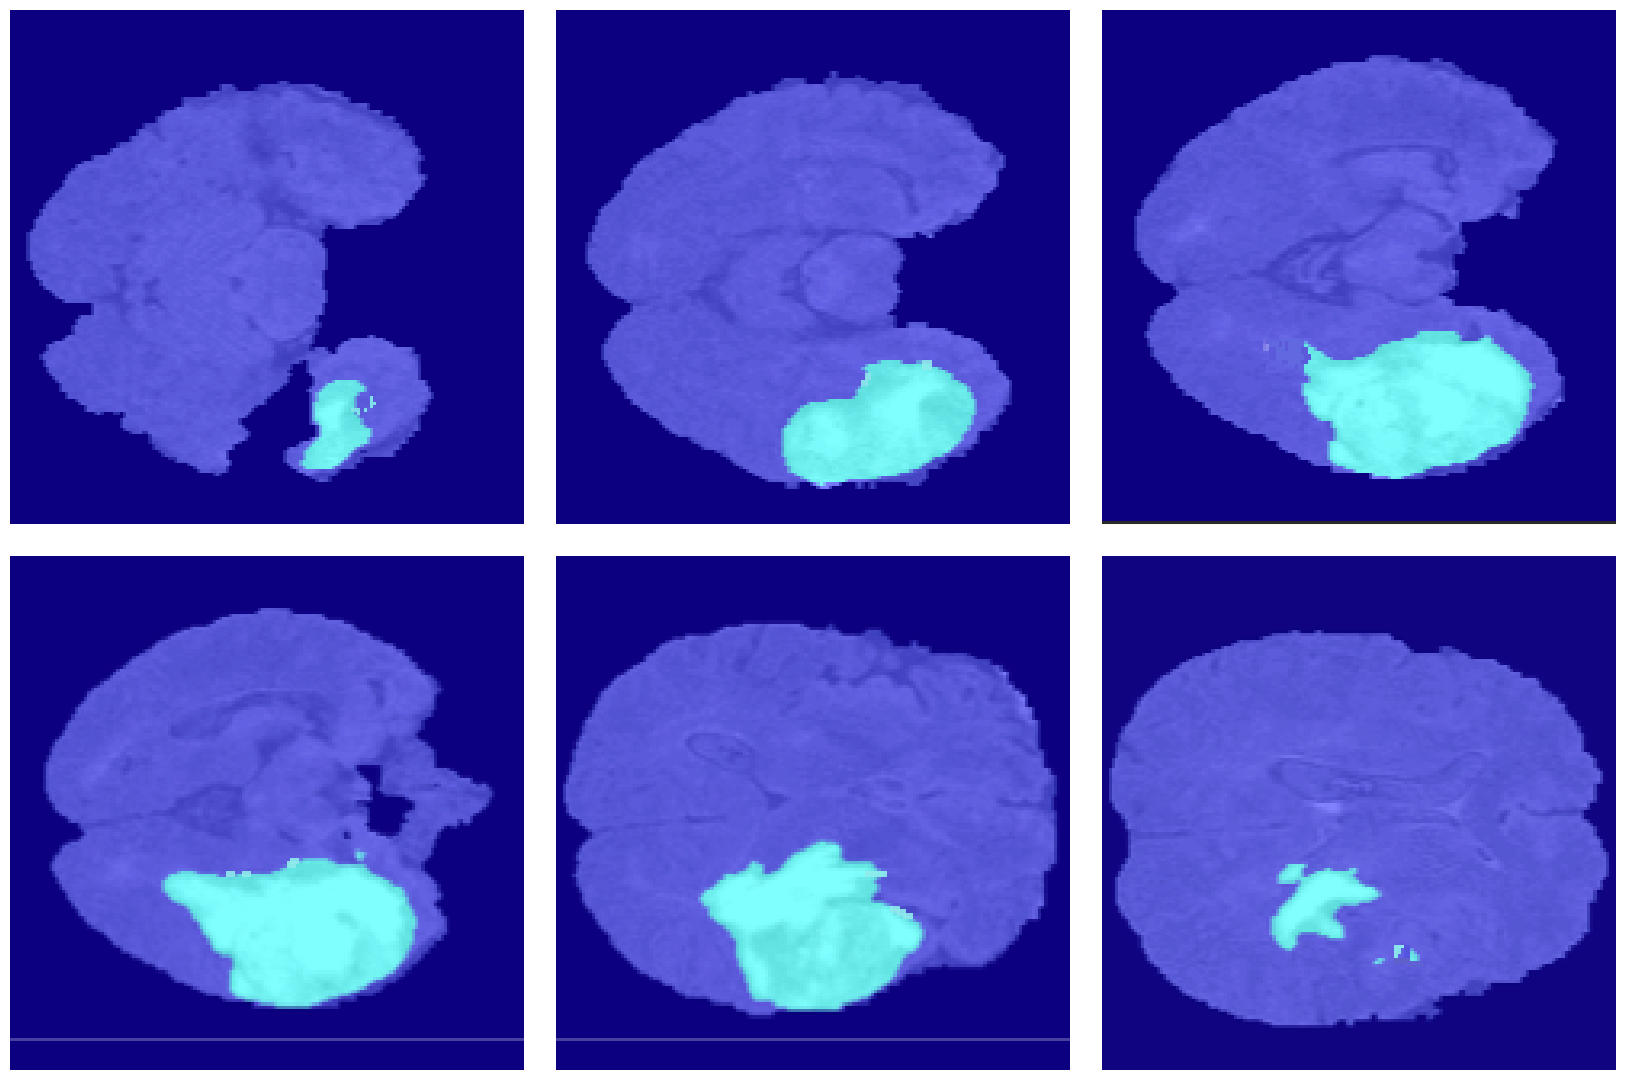

4.2. Segmentation Results

5. Discussion